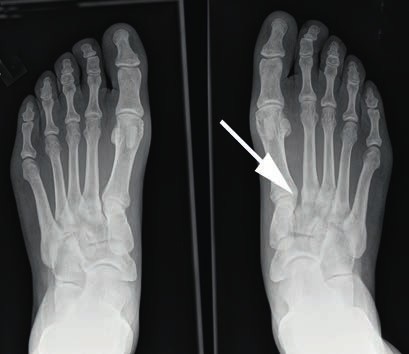

Mittelfußverletzungen im Sport, insbesondere Kapselbandverletzungen, haben in den letzten Jahren zugenommen 1 2 3. Dabei handelt es sich vor allem um Verletzungen des Lisfranc-Bandkomplexes. Der Lisfranc-Ligamentkomplex umfasst einen dorsalen und einen plantaren Anteil. Die Bandzüge verbinden das Os cuneiforme mediale mit der Metatarsale-II-Basis (Abb. 1). Das Ausmaß der Schädigung variiert stark – von der Zerrung bis hin zur vollständigen Zerreißung mit Diastase zwischen dem ersten und zweiten Metatarsale, ggf. auch mit Schädigung der angrenzenden Gelenkfiächen. Die leichteren und mittelschwer ausgeprägten Verletzungen werden häuflg erst verzögert diagnostiziert 4. Nicht selten sind diese Verletzungen Ursache langanhaltender Beschwerden und Sportunfähigkeit.

- Bei einer Grad-II-Verletzung findet sich in den Röntgenaufnahmen unter Belastung eine Diastase zwischen dem I. und II. Mittelfußknochen von 2 bis 5 mm. Die Seitenaufnahme des Fußes im Seitenvergleich ist unauffällig (Abb. 3). Im MRT kann eine partielle Ruptur der Bänder nachgewiesen werden. Nicht selten finden sich ab Grad-II-Verletzungen im MRT Ödeme der subchondralen Spongiosa der angrenzenden Gelenkflächen.

Bei Athleten tritt eine Verletzung des Lisfranc-Bandkomplexes typischerweise auf, wenn der Fuß bei gleichzeitiger Plantarflexion und leichter Rotation axial belast et wird 43 44. Die Zerreißung des Lisfranc-Bandkomplexes führt zu einer tarsometatarsalen Dehiszenz mit Dislokation der Metatarsale-II-Basis nach dorsal 45. Nunley und Vertullo (2002) 46 gehen in ihren Untersuchungen davon aus, dass es bei der Grad-I-Verletzung lediglich zu einer Distorsion des Lisfranc’schen Bandes in Verbindung mit einer Verletzung der Gelenkkapsel kommt. Aufgrund des in sich noch stabilen Kapselbandkomplexes finden sich normale Belastungsaufnahmen; die Verletzung der dorsalen Bandanteile lässt sich jedoch kernspintomografisch nachweisen 47. Bei der Grad-II-Verletzung kommt es zusätzlich zu einer vollständigen Zerreißung der dorsalen Bandanteile. Radiologisch zeigt sich dies durch das Auseinanderweichen von Os metatarsale I und II auf den Röntgenaufnahmen unter Belastung. Da die plantaren Kapselbandanteile intakt bleiben, kommt es jedoch zu keinem Absinken des Längsgewölbes in der Seitenaufnahme. Bei Grad-III-Verletzungen liegt eine komplette Zerreißung der dorsalen und plantaren Kapselbandstrukturen mit einem instabilen ersten Tarsometatarsalgelenk vor. Dies zeigt sich radiologisch durch ein Absinken des Längsgewölbes 48.